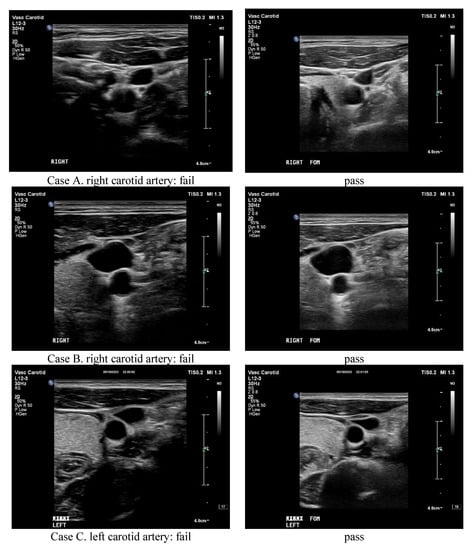

An ideal solution to solidify the Taguchi suggestion of any specific topic is either to verify or to testify in reality [13,24]. Therefore, three well-trained radiologists majoring in collecting ultrasound scan images were invited to be the reviewers of 32 pairs of scanned images taken from five volunteers on either the left or right carotid artery. Each pair of images had two corresponding images scanned from conventional or optimal settings, which were randomly submitted to the reviewers and graded as “fail” or “pass” according to their clearness and sharpness. Accordingly, the surveyed results are arranged in Table 5, and 5 out of 32 pairs of ultrasound scanned images are depicted in Figure 5. As clearly denoted in Table 5, a total of 192 images were graded (32 × 3 × 2 = 192), and the conventional combination of ultrasound preset gained 30 passes versus 66 passes for the optimal combination. Specifically, when each pair of scan slices was compared, 17 pairs of both conventional and optimal slices, 13 pairs of only optimal slices, and 2 pairs of only conventional slices passed the clinical criteria. Figure 5 also reveals the corresponding scan slices in this study. Pair A–D shows only one optimal pass, whereas pair E shows only one conventional pass that passed the clinical criteria.

Figure 5.

The ultrasound scanned images in this study. Pair (A–D) shows only one optimal pass, whereas pair (E) shows only one conventional pass that passed the clinical criteria.